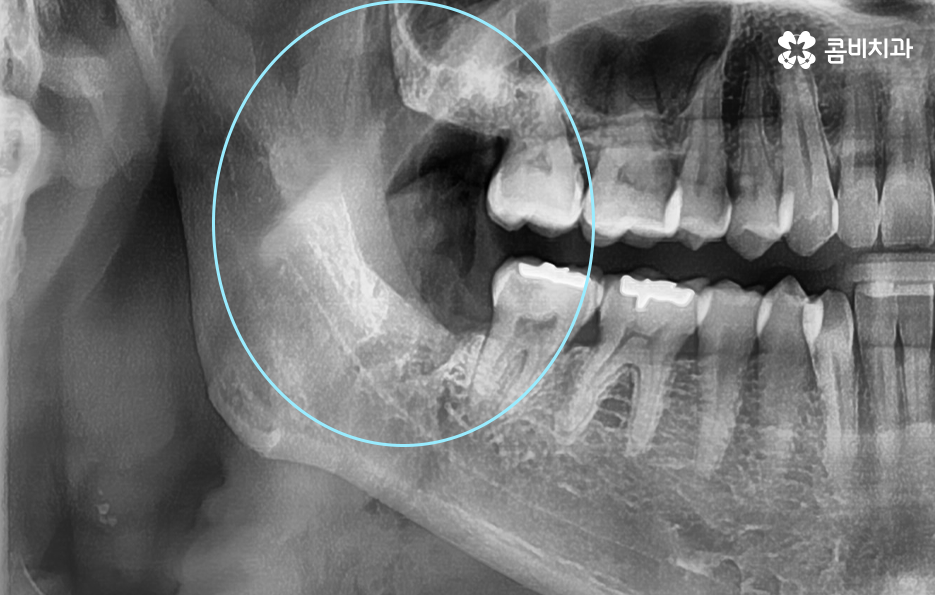

정상 맹출된 사랑니의 경우에도 청결관리가 쉽지 않지만 부분적으로 맹출된 매복사랑니의 경우 더욱 관리가 쉽지 않고 주변 잇몸이 쉽게 붓거나 염증이 발생하는 경우를 발견할 수 있는데요

매복사랑니 냄새의 경우 이처럼 청결관리가 잘 안되고 주변 잇몸에 염증이 발생하면서 증상이 심해지는 경우가 많기 때문에 예방적인 차원에서 발치를 고려해볼 필요가 있어요

매복사랑니의 경우 당장 발치가 필요하지 않은 경우에도 주기적으로 치과 검진을 통해 사랑니의 상태를 체크할 필요가 있으며 특히 어금니 뿌리 쪽에 안좋은 영향을 주고 있거나 우려가 있다면 발치 계획을 세워야 할 거예요

일반적으로 상악보다는 하악이 하치조 신경과 턱뼈가 근접하기 때문에 좀더 세심한 발치를 해야하며 정상 맹출된 사랑니 보다는 완전 매복되어 있는 사랑니 발치가 고난도의 발치로 분류되고 있어요